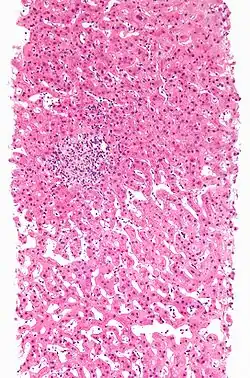

| Drug-induced hepatitis with granulomata. Other causes were excluded with extensive investigations. Liver biopsy. H&E stain. | |

Drug-induced hepatic granulomas are usually associated with granulomas in other tissues and patients typically have features of systemic vasculitis and hypersensitivity. More than 50 drugs have been implicated.

- Causes:

- Allopurinol, phenytoin, isoniazid, quinine, penicillin, quinidine